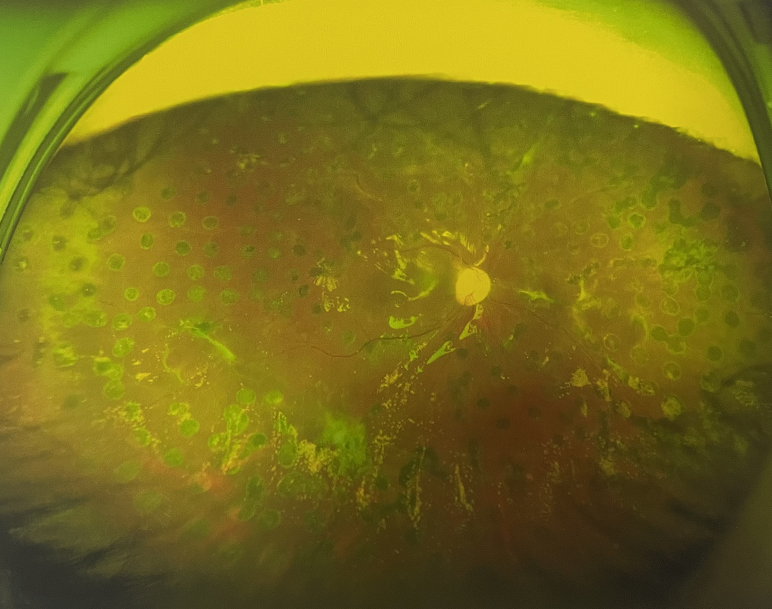

4個(gè)月后王女士來院取硅油,取油后視力恢復(fù)到0.6。“當(dāng)時(shí)來的時(shí)候真的只能看到模糊的影子,特別害怕覺得完了,想說眼睛估計(jì)要瞎了,沒想到手術(shù)后視力竟然提升了,現(xiàn)在也看得比較清楚了。”王女士說到。

張小虎醫(yī)生表示,糖網(wǎng)病進(jìn)展到嚴(yán)重增殖期帶來的視力損傷往往是極其嚴(yán)重的,目前王女士右眼從術(shù)前0.02恢復(fù)到術(shù)后0.6,已屬十分難得。

右眼術(shù)后